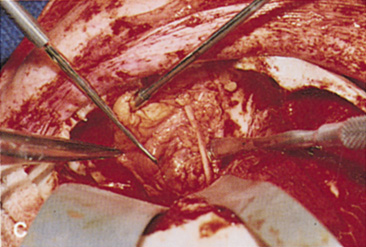

Fig. 14. A,B. Large intraorbital lymphangioma causing proptosis and optic nerve compression

in a 2-year-old child. C. View of the left orbit from above after removal of the frontal bone flap, including

the supraorbital rim and orbital roof. An extensive exposure

of the entire superior and lateral orbit is afforded. The levator

and superior rectus complex is being retracted laterally with a muscle

hook, whereas the Freer elevator retracts the superior oblique muscle

medially. The frontal nerve can be seen running from posterior to anterior

over the superior orbit. The orbital mass is exposed in this fashion. D. The fronto-orbital bone flap is wired back in place after completion of

the procedure. E. Postoperative appearance of the patient. F. The postoperative CT scan shows complete removal of the lymphangioma. This

large and diffuse lesion would have been difficult to remove with